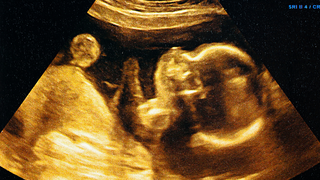

Fertility concerns are a primary reason individuals choose surgery. Endometriosis can affect the ovaries, fallopian tubes, and uterus, making conception difficult. Surgery can improve fertility outcomes by clearing lesions and restoring normal anatomy.